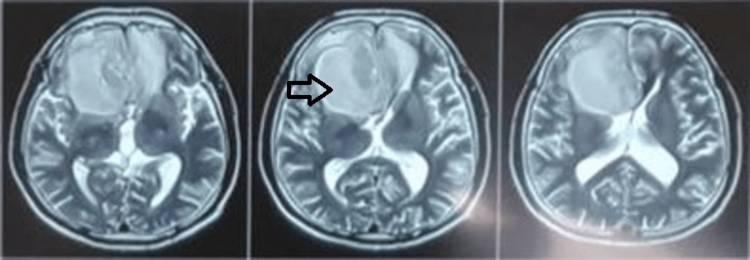

术后,患者未出现神经功能缺损。后续CT扫描显示胼胝体和双额叶轻度肿胀,手术部位无血肿迹象(图7)。对脓肿排出的脓液进行培养和敏感性测试,证实存在对万古霉素敏感的金黄色葡萄球菌。患者症状明显改善,出院后接受抗生素治疗。不幸的是,患者在收到医院的组织病理学报告后失去了随访,尽管建议辅助放化疗。

图7 术后CT脑(平片);脓肿壁完全切除,无手术部位血肿